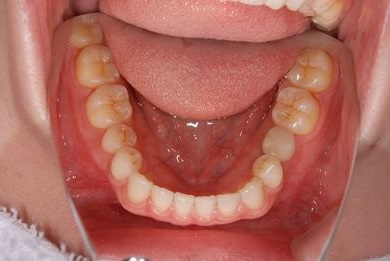

インプラントの症例写真 IMPLANT

インプラント治療

| 性別/年齢 | 女性 / 29歳 | ||||||||||||||||||||||||||||||||

| 主訴 | インプラント治療と、親知らずの抜歯の相談。なるべく安価で、短期間で終了して欲しい。 | ||||||||||||||||||||||||||||||||

| 治療方針 | 欠損部分をインプラント治療にて、機能的・審美的回復を行う。 | ||||||||||||||||||||||||||||||||

| 治療内容 | インプラント1本、メタルボンドセラミッククラウン1本 | ||||||||||||||||||||||||||||||||

| 総治療費 | 252,000円 | ||||||||||||||||||||||||||||||||

| 治療期間 | 11ヶ月 |